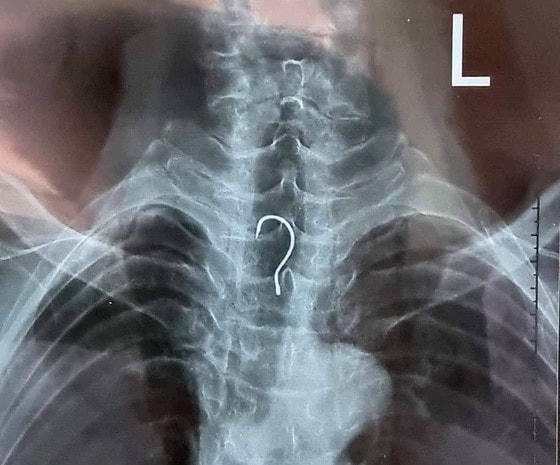

Ngày 15/12, nguồn tin từ Bệnh viện Đa khoa tỉnh Hà Tĩnh, các y bác sĩ của bệnh viện này vừa tiến hành nội soi và gắp thành công dị vật là một chiếc lưỡi câu dài khoảng 4cm mắc trong thực quản của bệnh nhân T.V.A. (83 tuổi, trú tại xã Kỳ Phong, huyện Kỳ Anh, tỉnh Hà Tĩnh).

Ngay sau đó, ê-kíp nội soi đã gắp ra ngoài dị vật là một chiếc lưỡi câu có chiều dài khoảng 4cm, vòng cung rộng gần 1,5cm.